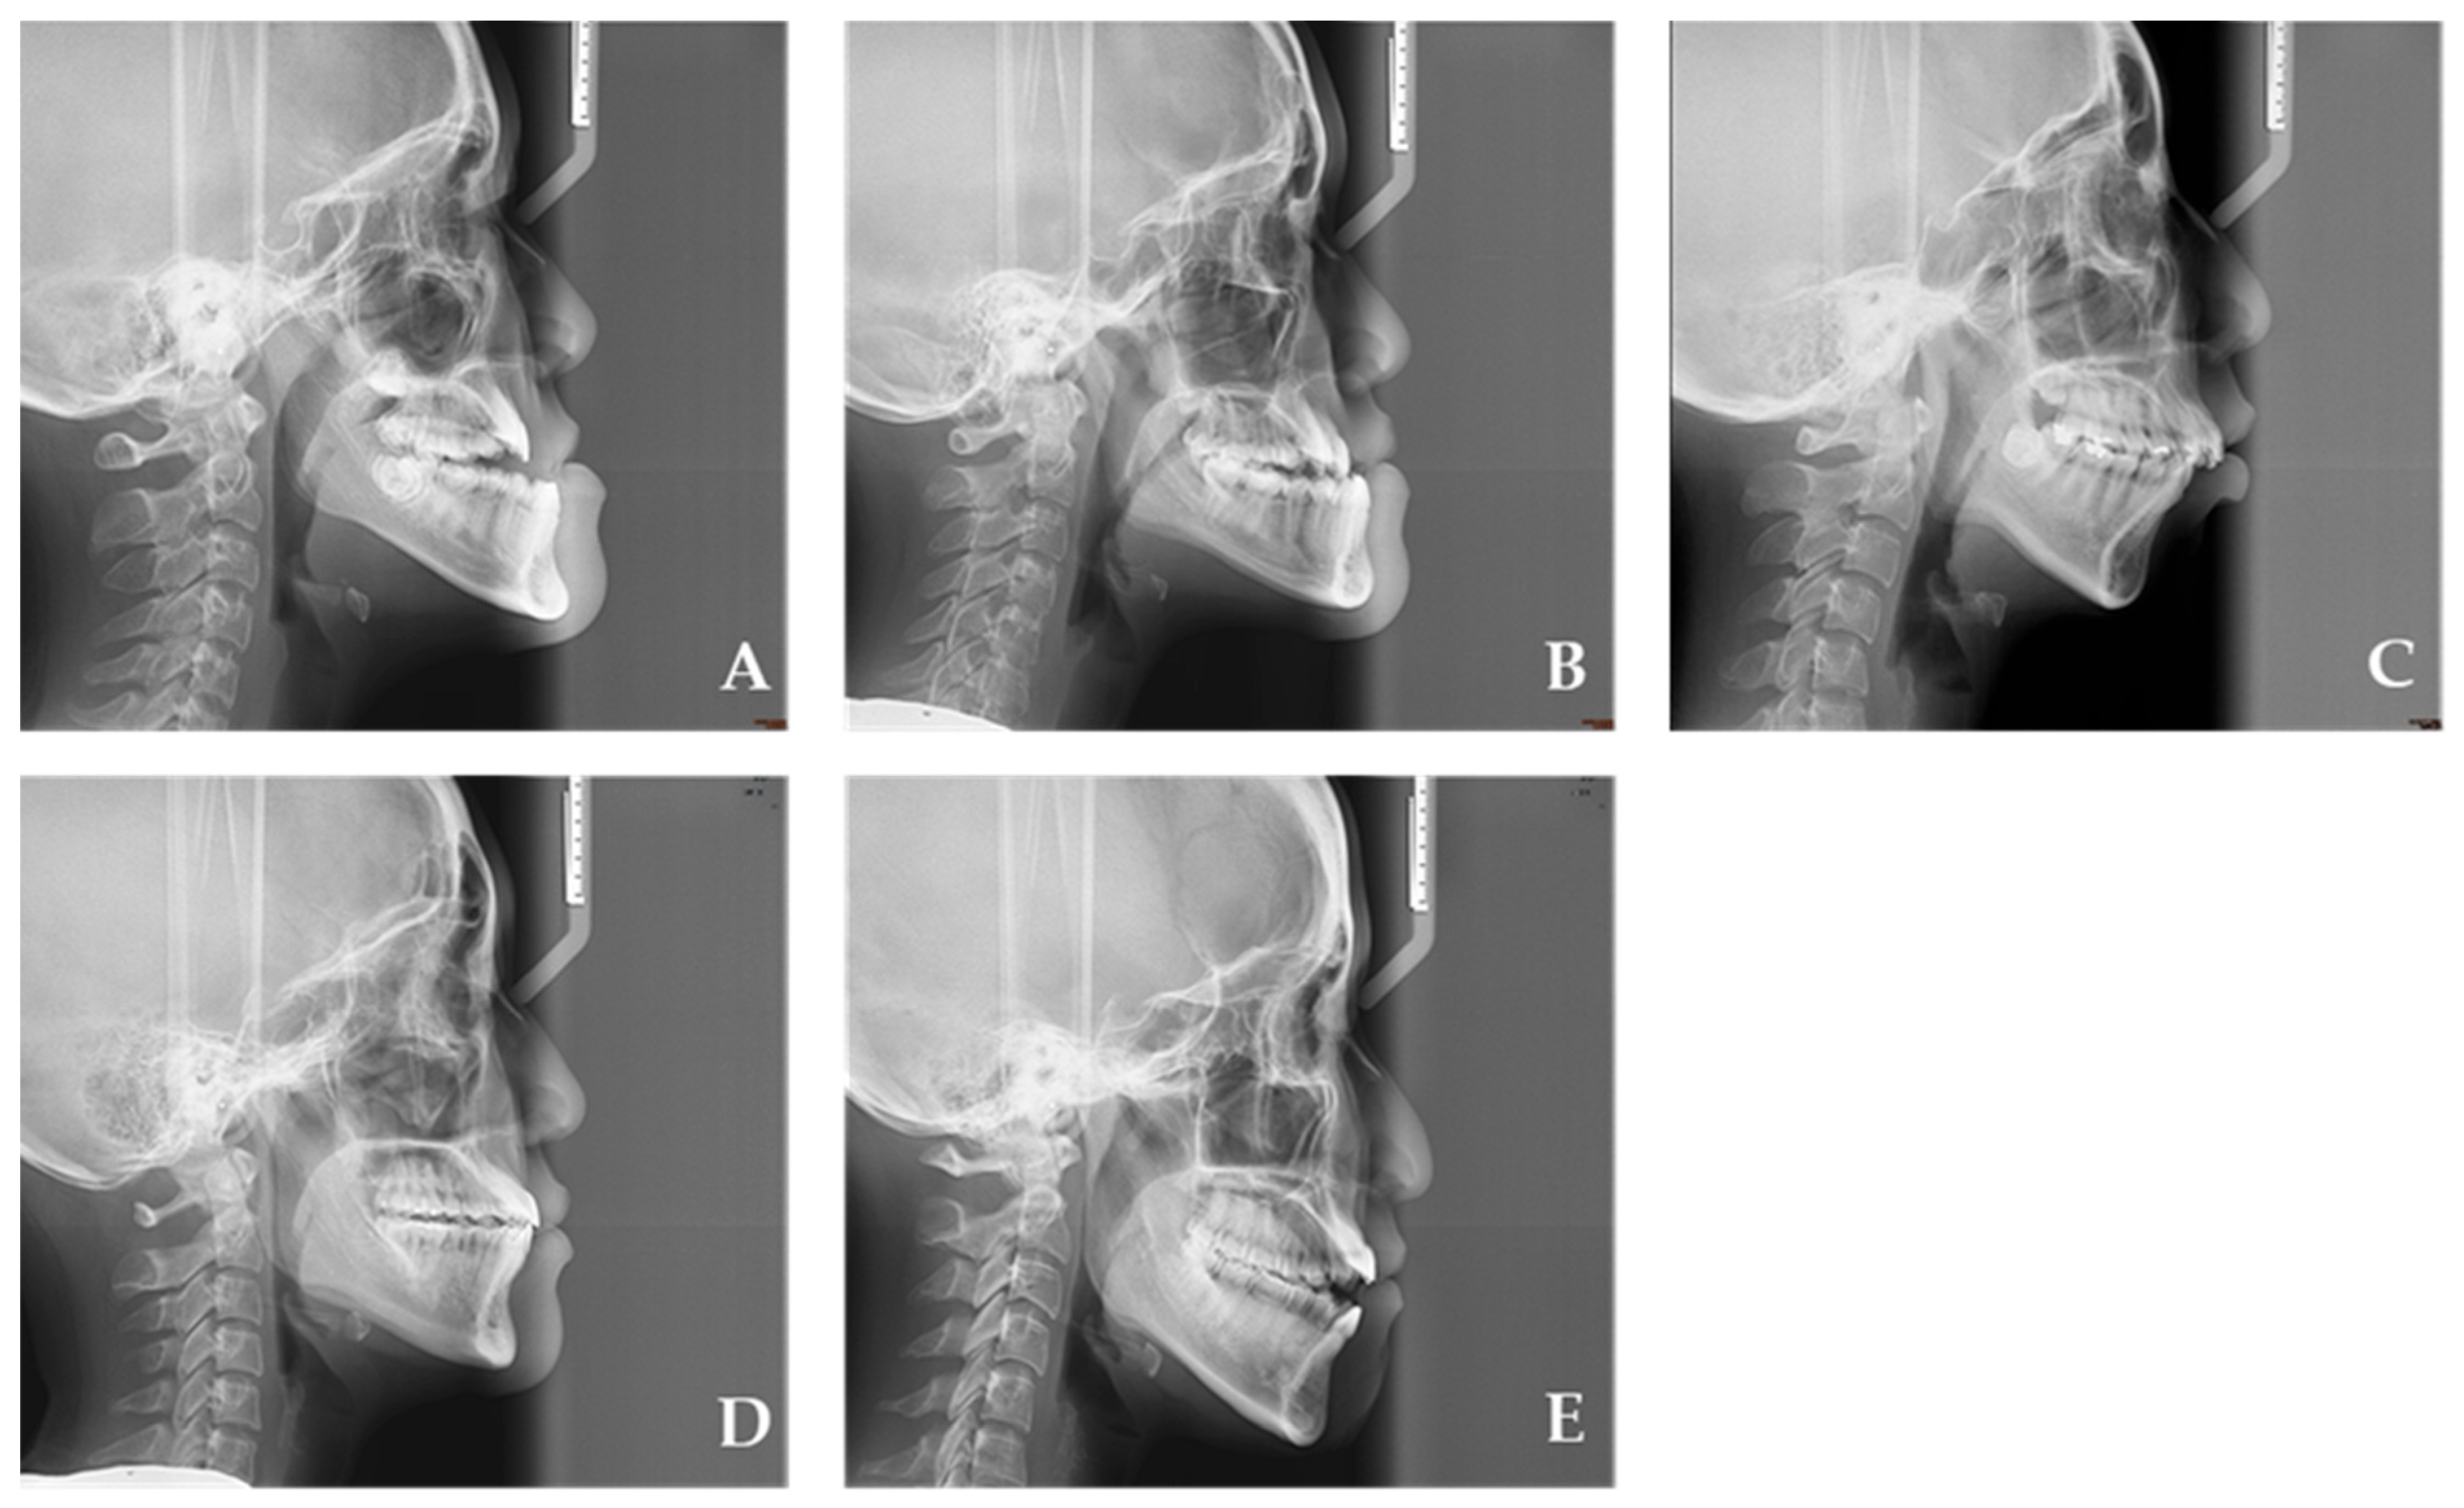

The patients were categorized into five groups representing different developmental stages (Figure 1): Group 1 (early adolescence, 10–13 years), Group 2 (middle adolescence, 14–17 years), Group 3 (late adolescence, 18–21 years), Group 4 (early adulthood, 22–30 years), and Group 5 (middle adulthood, 31–50 years). Additionally, skeletal relationships were classified into three classes: Class I (ANB angle = 0° to 4°), Class II (ANB angle > 4°), and Class III (ANB angle < 0°).

Figure 1. (A): Group 1 (early adolescence), (B): Group 2 (middle adolescence), (C): Group 3 (late adolescence), (D): Group 4 (early adulthood), and (E): Group 5 (middle adulthood).